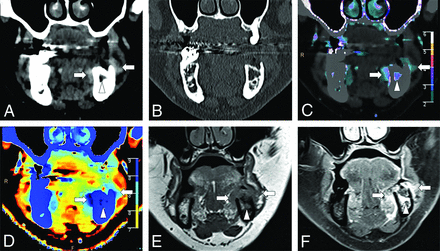

Conventional (A), iodine density (B), and Z-effective (C) images illustrating an ROI placed over a right tongue base squamous cell carcinoma. ROI size is 4.89 mm in diameter (ED), with an average area (Av) of 18.76 mm2. ROI measurements were obtained over 3 image slices (not shown), with the average iodine and Z-effective values calculated. A right level IIa cystic nodal metastasis is also present (not labeled).

A 61-year-old man with left oral tongue squamous cell carcinoma (arrow) seen on a conventional CT image (A). Iodine density (B), color iodine density overlay (C), and Z-effective (D) images show markedly improved contrast resolution of the tumor from the surrounding normal oral tongue mucosa. The left oral tongue tumor has an iodine density = 2 mg/mL and a Z-effective value = 8.33. Normative oral tongue mucosa values from the healthy control cohort are iodine density = 0.92 mg/mL and Z-effective value = 7.67.